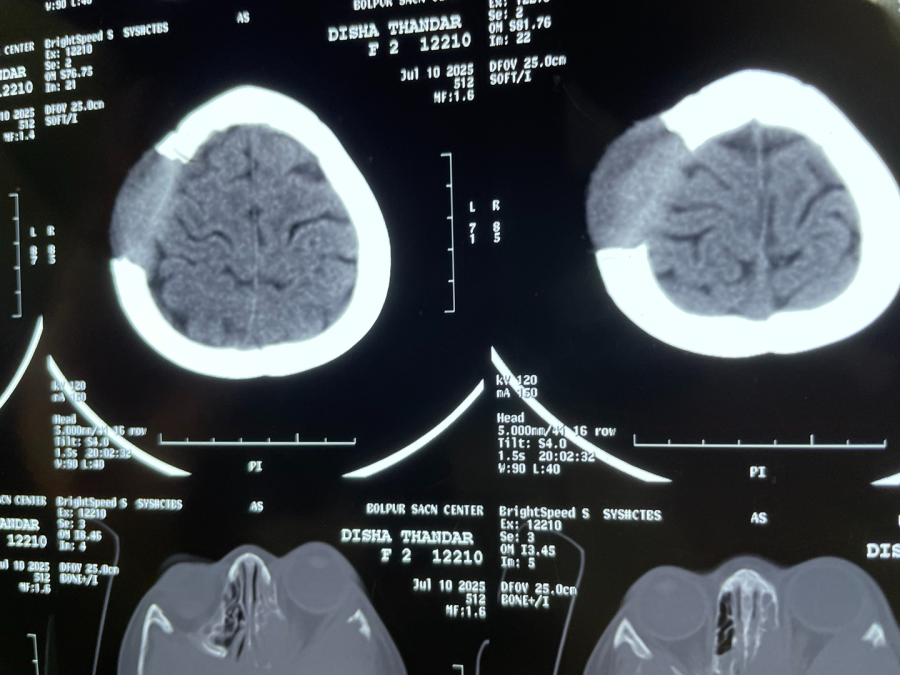

Ein 2-jähriges Mädchen mit einem Gehirntumor, der bereits die Schädeldecke durchbrochen hatte und ein Auge nach vorne vorwölbte, wurde zu uns gebracht. Die Eltern hatten in Kalkutta kein Krankenhaus finden können, das dieses Kind behandeln kann. Der Vater hat sein Toto verkauft, um all die Kosten zu bezahlen. So kann er nicht mehr als Fahrer sein Einkommen verdienen und muss als Feldarbeiter sich verdingen.

Wir waren auch erstmal hilflos, hatten aber eine MRT-Diagnostik gemacht und schickten es zu unserem Neurologen Dr. Swapan, der sich diesem Kind mit Herzblut annahm und eine Histiocytose vermutete. Mit unserem Onkologen Dr. Pandit konnten wir dies weiter abklären. Es sei ein gutartiger Tumor, so die Vermutung – die notwendige Behandlung soll nun eingeleitet werden…